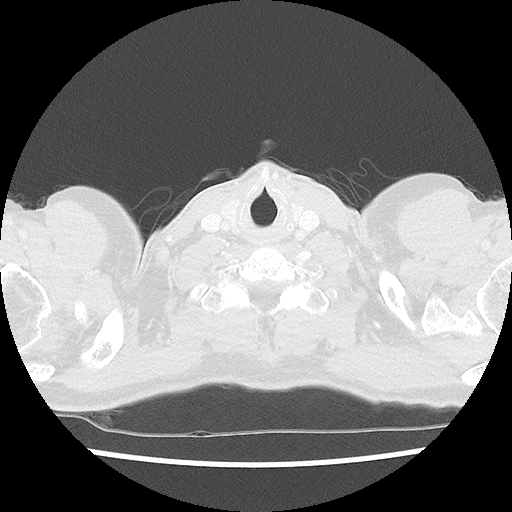

Trots als ik ben kan ik weer de binnenkant van mijn lichaam delen. Opnieuw zonder knobbels en bobbels, gewoon een super gezond lichaam van een jonge 50er.

Hierbij dus weer een mooi inzicht in mijn lichaam, ik ben er blij mee!

Zo knap dat de artsen op deze films kunnen zien of er iets mis is..

Voor mij is het een Onderwater opname

Geweldig dat dit bestaat en de artsen er raad mee weten!

Knap hoor, zeker als je te horen krijgt dat alles goed is!!